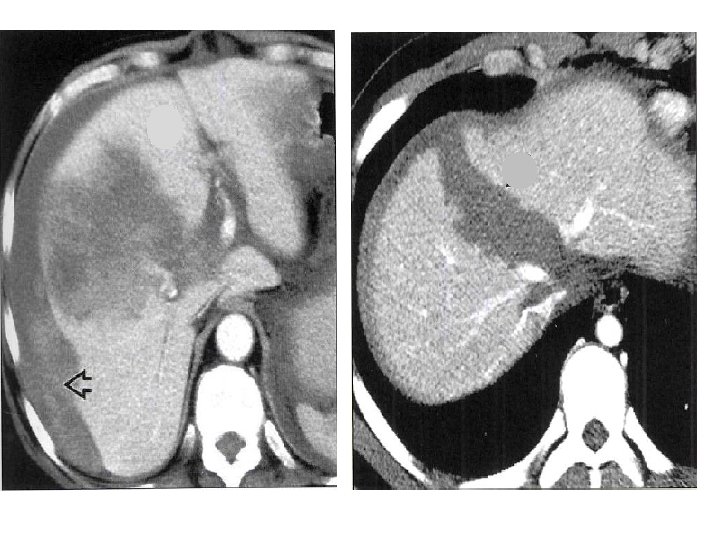

Caso clínico • - JCC, sexo masculino. • - Vítima de acidente automobilístico • - Dor Abdominal

• Conduta clínica: Optado por tratamento conservador das lesões hepáticas, com acompanhamento clínico e controle de hematócrito. • 06 dias após o trauma: • Paciente evolui estável, porém apresentando pico febris. • Solicitado exame para controle das lesões hepáticas e pesquisa de coleções